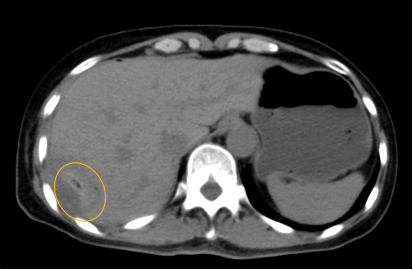

入院后,影像診療中心立即給李女士完善了CT和MR檢查,發(fā)現(xiàn)病變位于肝包膜下,臨近膈肌,消融治療過程中有并發(fā)損傷膈肌的可能,難度較大,但是采用精準(zhǔn)影像定位是可以完成的。陳寶瑩主任立即與腫瘤三病區(qū)劉金鵬主任聯(lián)系,并與影像微創(chuàng)治療小組進行MDT討論:患者為卵巢癌肝右葉包膜下單發(fā)轉(zhuǎn)移瘤,最長徑不超過3cm,患者對局部治療的主觀愿望強烈,符合消融治療專家共識,遂制定了影像引導(dǎo)下局部消融治療聯(lián)合全身治療的綜合治療方案。

針對這個特殊部位的腫瘤,要想消融完全,那么膈肌損傷的風(fēng)險就很高,陳寶瑩主任帶領(lǐng)影像微創(chuàng)亞專業(yè)組成員仔細閱讀CT圖像,設(shè)計進針路徑,結(jié)合MR圖像確定腫瘤活性范圍,制定了周密而詳盡的消融計劃。臘月二十九,即住院第二天影像微創(chuàng)治療小組圓滿為患者完成了腫瘤微波消融治療,觀察24小時后出院回家過年。術(shù)后48小時隨訪患者無明顯不適,術(shù)后7天隨訪,患者肝功、血常規(guī)等各項指標(biāo)均恢復(fù)正常。